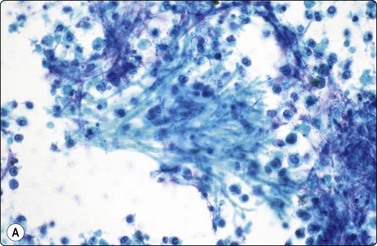

image image

Fig. 18.18 Pneumocystis

(A) granular foamy aggregate of 5-micron cup-shaped cysts (Pap, ×400); (B) Aggregated cup-shaped cysts with dot nuclei (GMS, ×400).